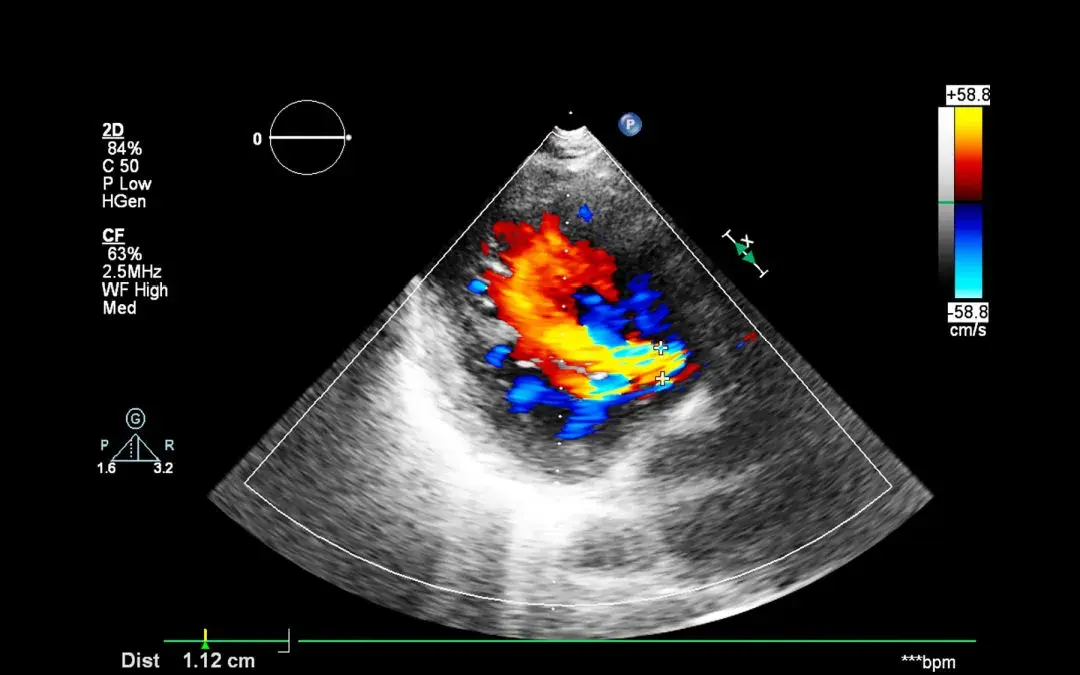

Color Doppler echocardiography is a test that helps cardiologists see the blood flow in the heart and its chambers more clearly than a regular echocardiography.

In simple terms, it uses colors to show the direction of the blood flow — red means the blood is flowing toward the probe, and blue means it’s flowing away from it. This is different from a regular echocardiography, which shows blood flow in black and white.

In Doppler echocardiography, the moving objects are blood cells — when the blood cells move toward the probe, they will appear red on the screen. If they are moving away from the probe, they will appear blue.

When a heart is healthy, the blood flow appears in two distinct colors — blue and red. However, when the heart is in a diseased state, such as when there is a leak in the valves, the blood flow can appear mosaic in color with shades of yellow added to it.

This diagnostic tool is very useful in identifying leaks and blockages in valves, as well as abnormalities in the flow of blood and defects between the walls of the heart chambers.

The mosaic-colored jets seen on color Doppler are an important visual indicator of these changes. Even small defects can be easily detected with this technique, making it a valuable tool in the early detection and treatment of heart disease.